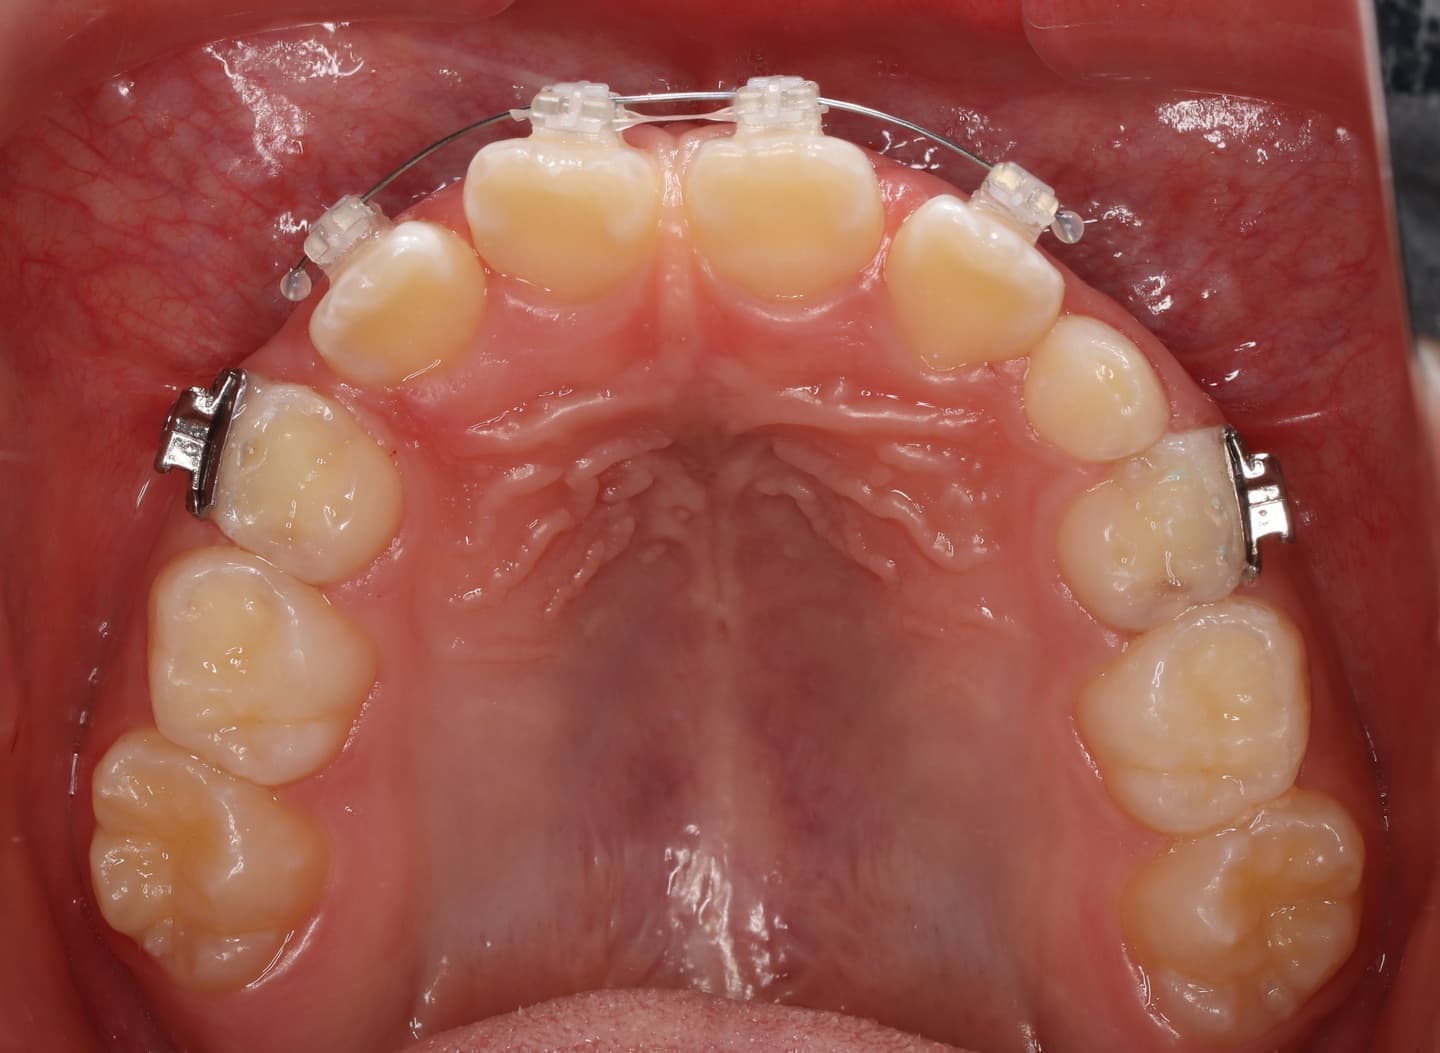

治療後(12ヶ月後)

治療中